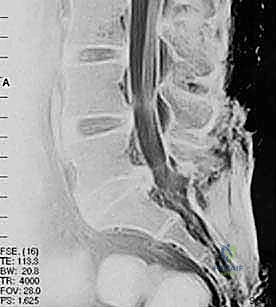

لفهم كيفية عمل تقنيات PLIF و TLIF، يجب أولاً فهم تشريح العمود الفقري القطني. يتكون الجزء السفلي من الظهر من خمس فقرات قطنية (L1 إلى L5). بين كل فقرة وأخرى يوجد "قرص غضروفي" (Disc) يعمل كوسادة لامتصاص الصدمات وتسهيل الحركة. يمر الحبل الشوكي والأعصاب الشوكية عبر قناة عظمية تُسمى "القناة الشوكية".

عندما تتآكل هذه الأقراص الغضروفية بسبب التقدم في العمر أو الإصابات، أو عندما تتحرك الفقرات من مكانها الطبيعي، يحدث تضيق في القناة الشوكية أو ضغط مباشر على جذور الأعصاب. هذا الضغط الميكانيكي هو المسبب الرئيسي للألم المبرح الذي يمتد غالبًا إلى الساقين (ما يُعرف بعرق النسا).

- تضيق القناة الشوكية القطنية (Lumbar Spinal Stenosis): تضيق المساحة التي تمر بها الأعصاب بسبب النتوءات العظمية أو تضخم الأربطة، مما يسبب ألماً شديداً عند المشي أو الوقوف.

- الانزلاق الفقري (Spondylolisthesis): انزلاق فقرة فوق الفقرة التي تحتها، مما يسبب عدم استقرار ميكانيكي وضغطاً عصبياً.

- مرض القرص التنكسي (Degenerative Disc Disease): تآكل الغضاريف بشكل حاد يؤدي إلى احتكاك العظام ببعضها البعض.